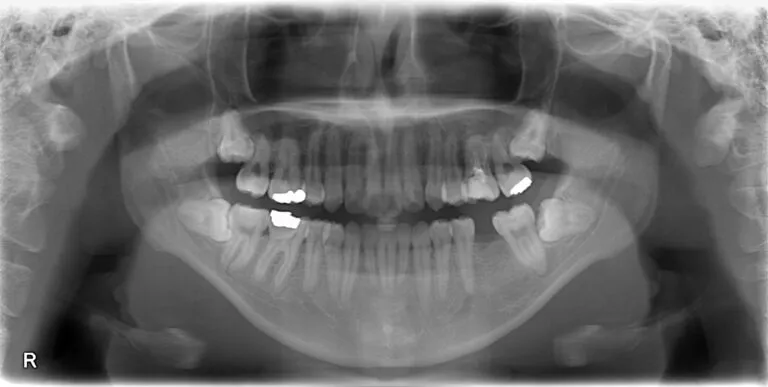

原因の本当に悪い歯はどれなのかの特定のためにレントゲン写真を撮ります。

問診、打診(歯をそれぞれ叩いて痛みがないかの確認)及び、目視とレントゲン所見から左上6番目の歯が原因であると診断できました。